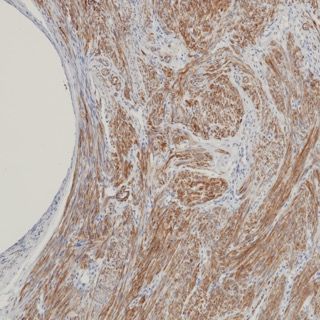

IHC

Caldesmon